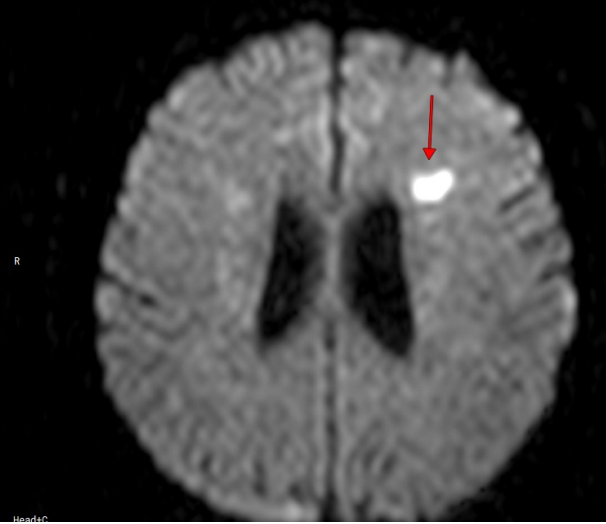

Дыра в моей голове. Остальные в другом полушарии. Повезло, что некрупная

Я согласно киваю, и решаю не объяснять собеседнице, что мне 48 и я чуть больше двух месяцев назад блукала в речи, не могла связать пары слов - короче, перенесла инсульт. И, судя по МРТ, даже не один.

Поэтому все, что я могу - это с завистью глядеть вслед стройной девушке, которая легко бежит мимо нас, вдоль озера. Вот когда надо было о здоровье-то думать, а сейчас я все-таки маленько запоздала. И дырки в моей голове, на снимках МРТ - тому подтверждение. Впрочем, все, что я могу теперь сделать - это принять существующее положение, как данность, регулярно измерять давление, пить препараты, ну и в качестве эксперимента заменить с т а т и н ы ходьбой.